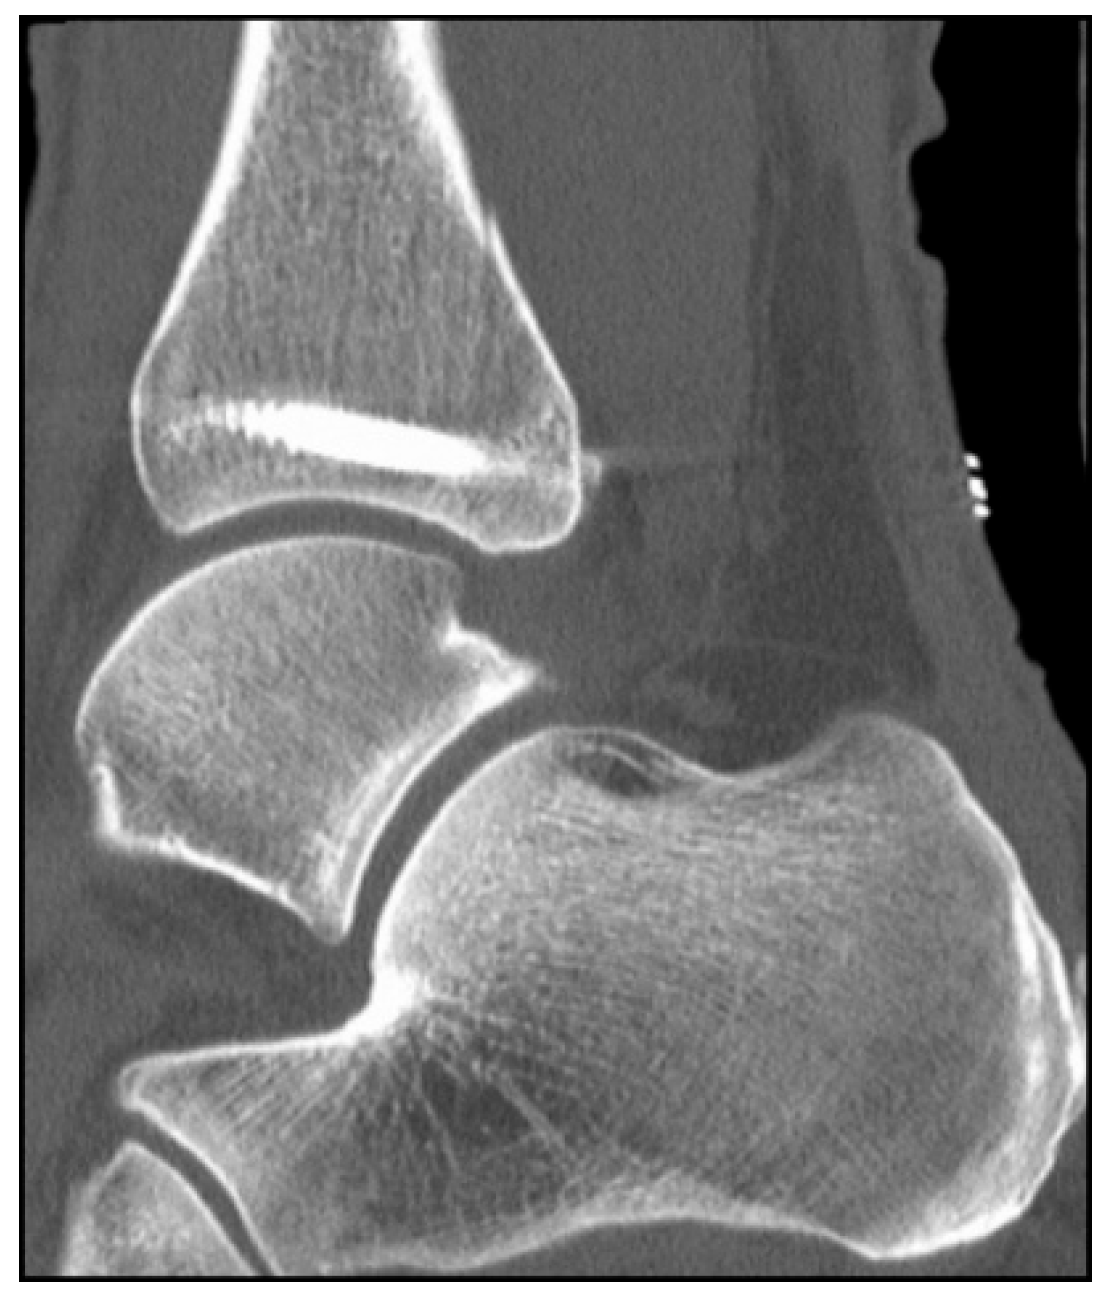

2. Preoperative Diagnostics

5.2. Inside-Out Fixation of the Posterior Malleolus Using a Headless Double-Threaded Compression Screw